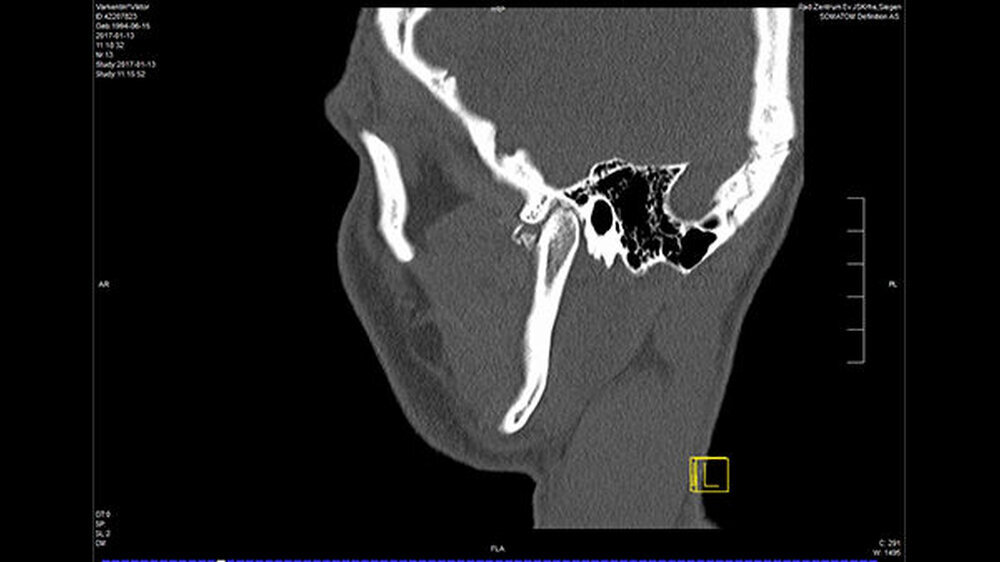

In der Folge entwickelte sich binnen fünf Monaten eine absolute Mundöffnungsbehinderung. Die SKD betrug null Millimeter. Passend zur klinischen Symptomatik zeigten sich radiologisch die Zeichen einer knöchernen Ankylose der Kiefergelenke beidseits Typ III nach Sawhney [1986] (Abbildung 1a-d).